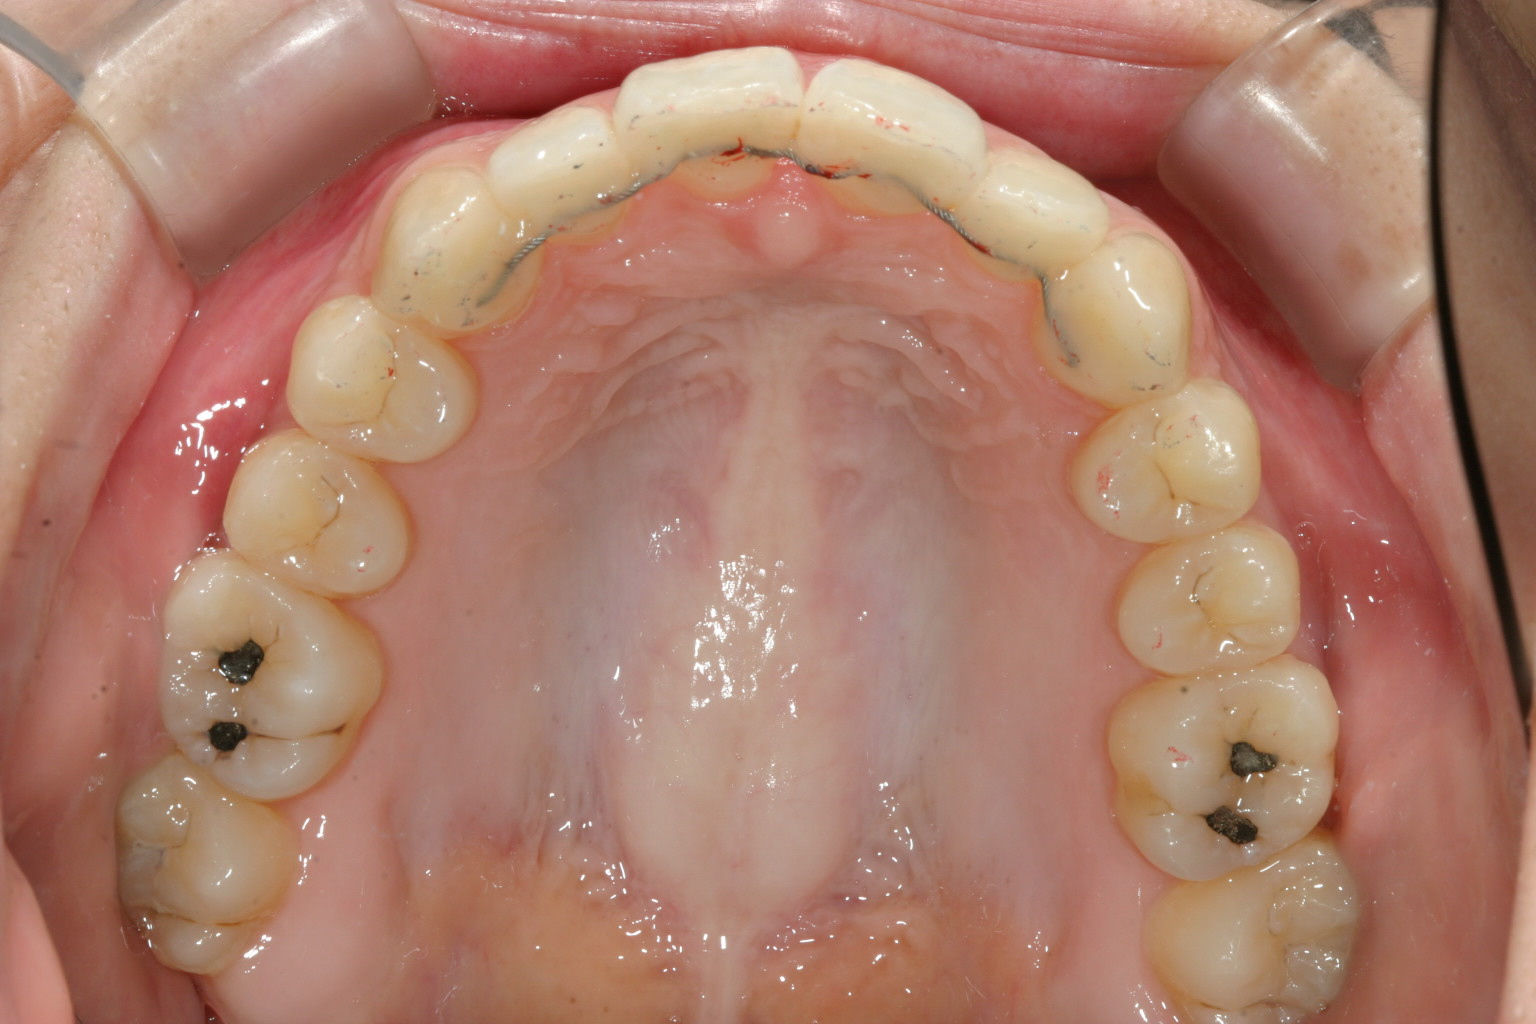

上顎のアーチをU字に変えて綺麗に配列しました。